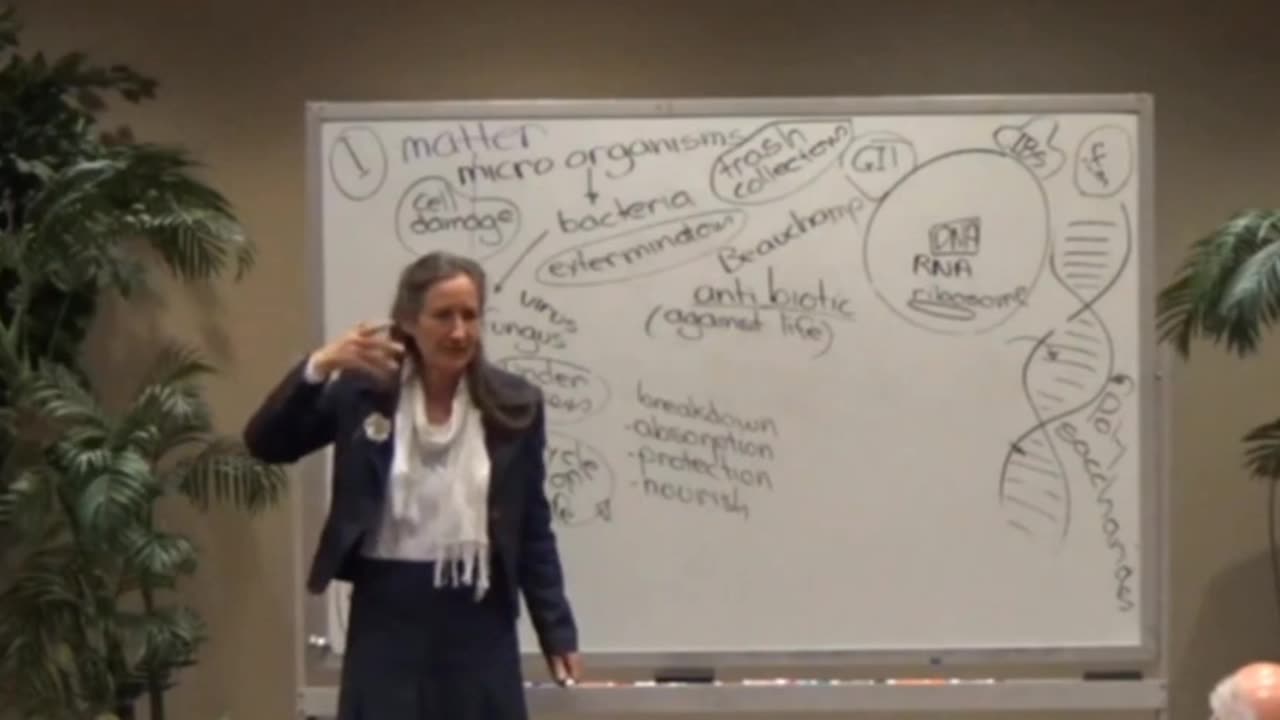

Microbiome & the Gut Brain

BARBARA O’NEILL WHAT ARE BONES MADE OF?

Barbara ONeill -Recipe for Flu Bomb